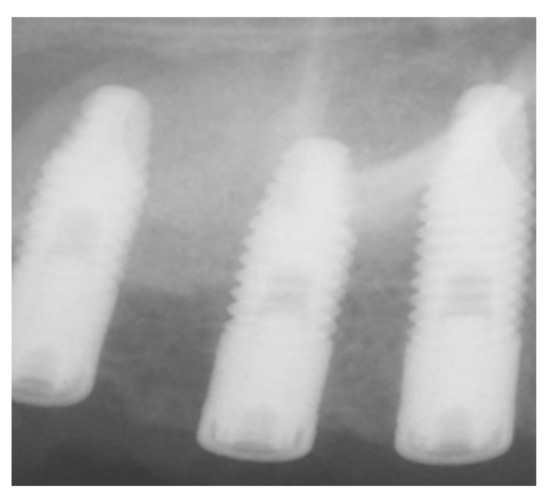

| External | 120 | 51.3 |

| Internal | 114 | 48.7 |

| Implant diameter (mm) | ||

| 3.5 | 31 | 13.3 |

| 4 | 162 | 69.2 |

| 5 | 41 | 17.5 |

| Implant length (mm) | ||

| 8 | 7 | 3 |

| 10 | 95 | 40.6 |

| 12 | 132 | 56.4 |